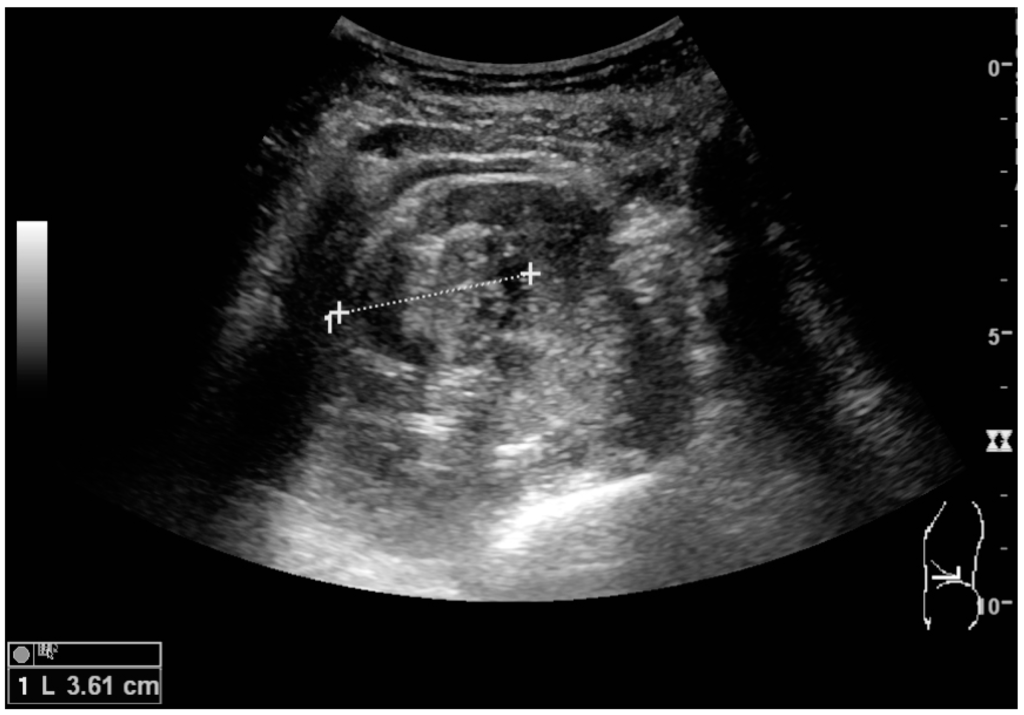

Figure 5. Simple cyst with posterior enhancement in an adult kidney. Measurement of kidney length on the US image is illustrated by ‘+’ and a dashed line.